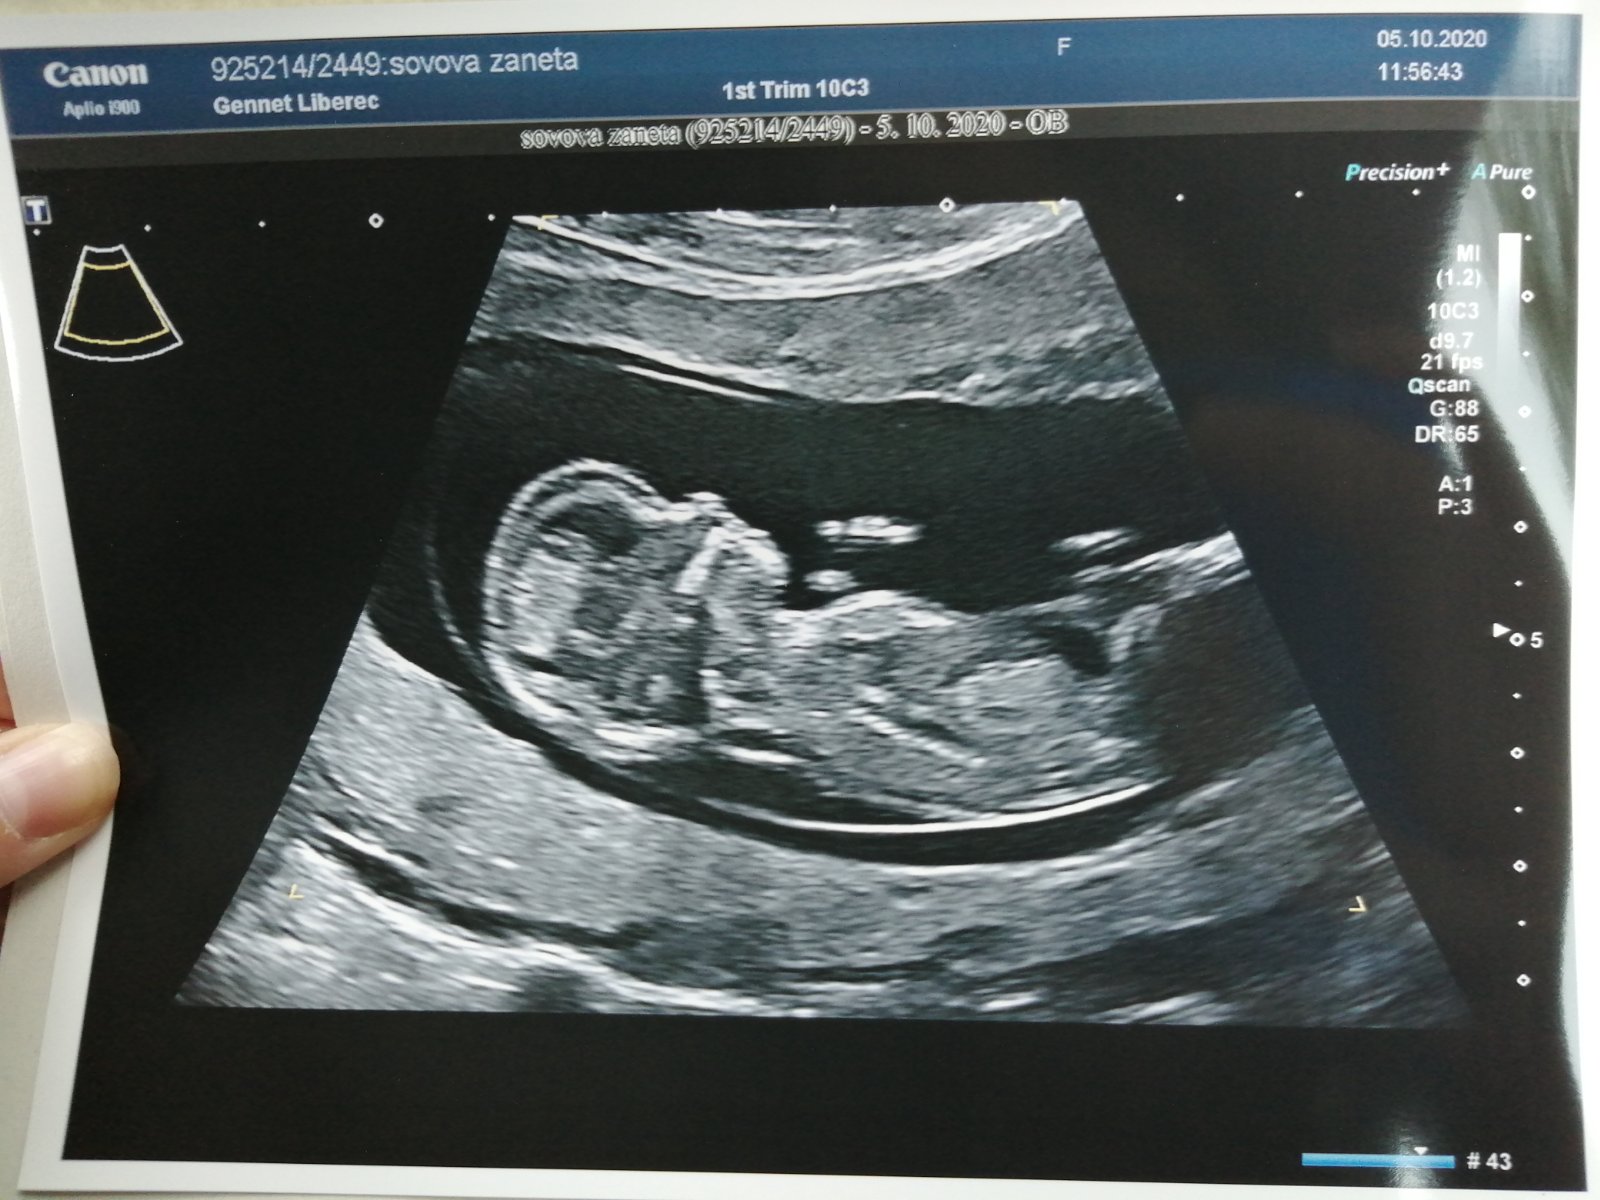

Jo a na 85% nám řekly holčičku 😃💗👶🏻❤️

Ahojky tety první screening dopadl dobře termín porodu máme 13.4.2021 a tím že jsem brala progesteron tak jsem měla vysokou hodnotu fshcg, ale prý to dělá ten progesteron, tak se mám dohodnout s dr. až půjdu na kontrolu zda nebude lepší jít na jeďte jedny kontrolní testy 🙂 Odpovídáme 12+6tt takže za 3dny odstartujeme 4.mesic 😍